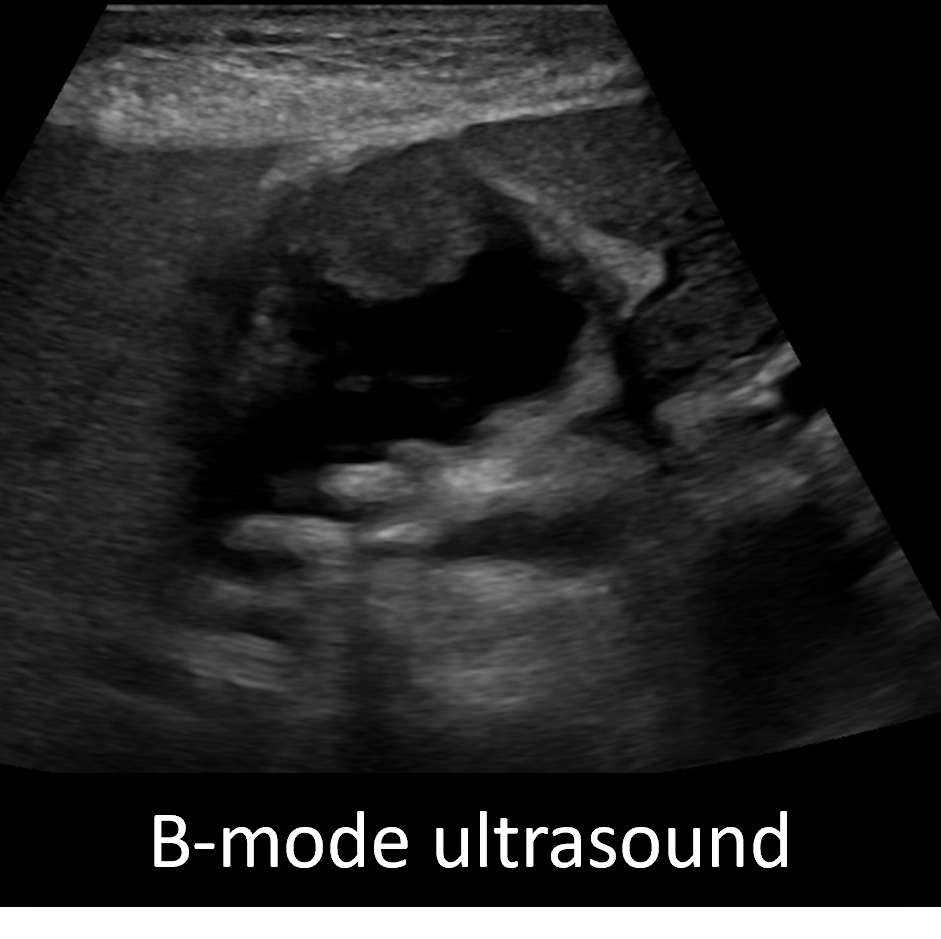

Challenge yourself with a case brought to you by Malak Itani, MD @ItaniMalak from @WashUMedMIR: 70M with RUQ pain x 1 week with nodular thickening of the GB wall, superimposed on changes of cholecystitis on initial CT, s/p cholecystostomy tube on MR.